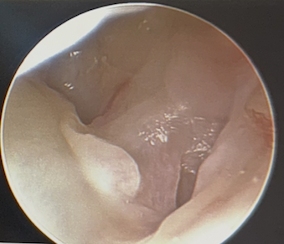

Ulna / foveal sided TFCC tear on arthroscopy

Technique

- viewing via 3-4 portal

- instrumentation via 6R +/- 6U portal (either side of ECU)

- pass outside in and suture over capsule

- suture anchor repair

- drill hole in ulna